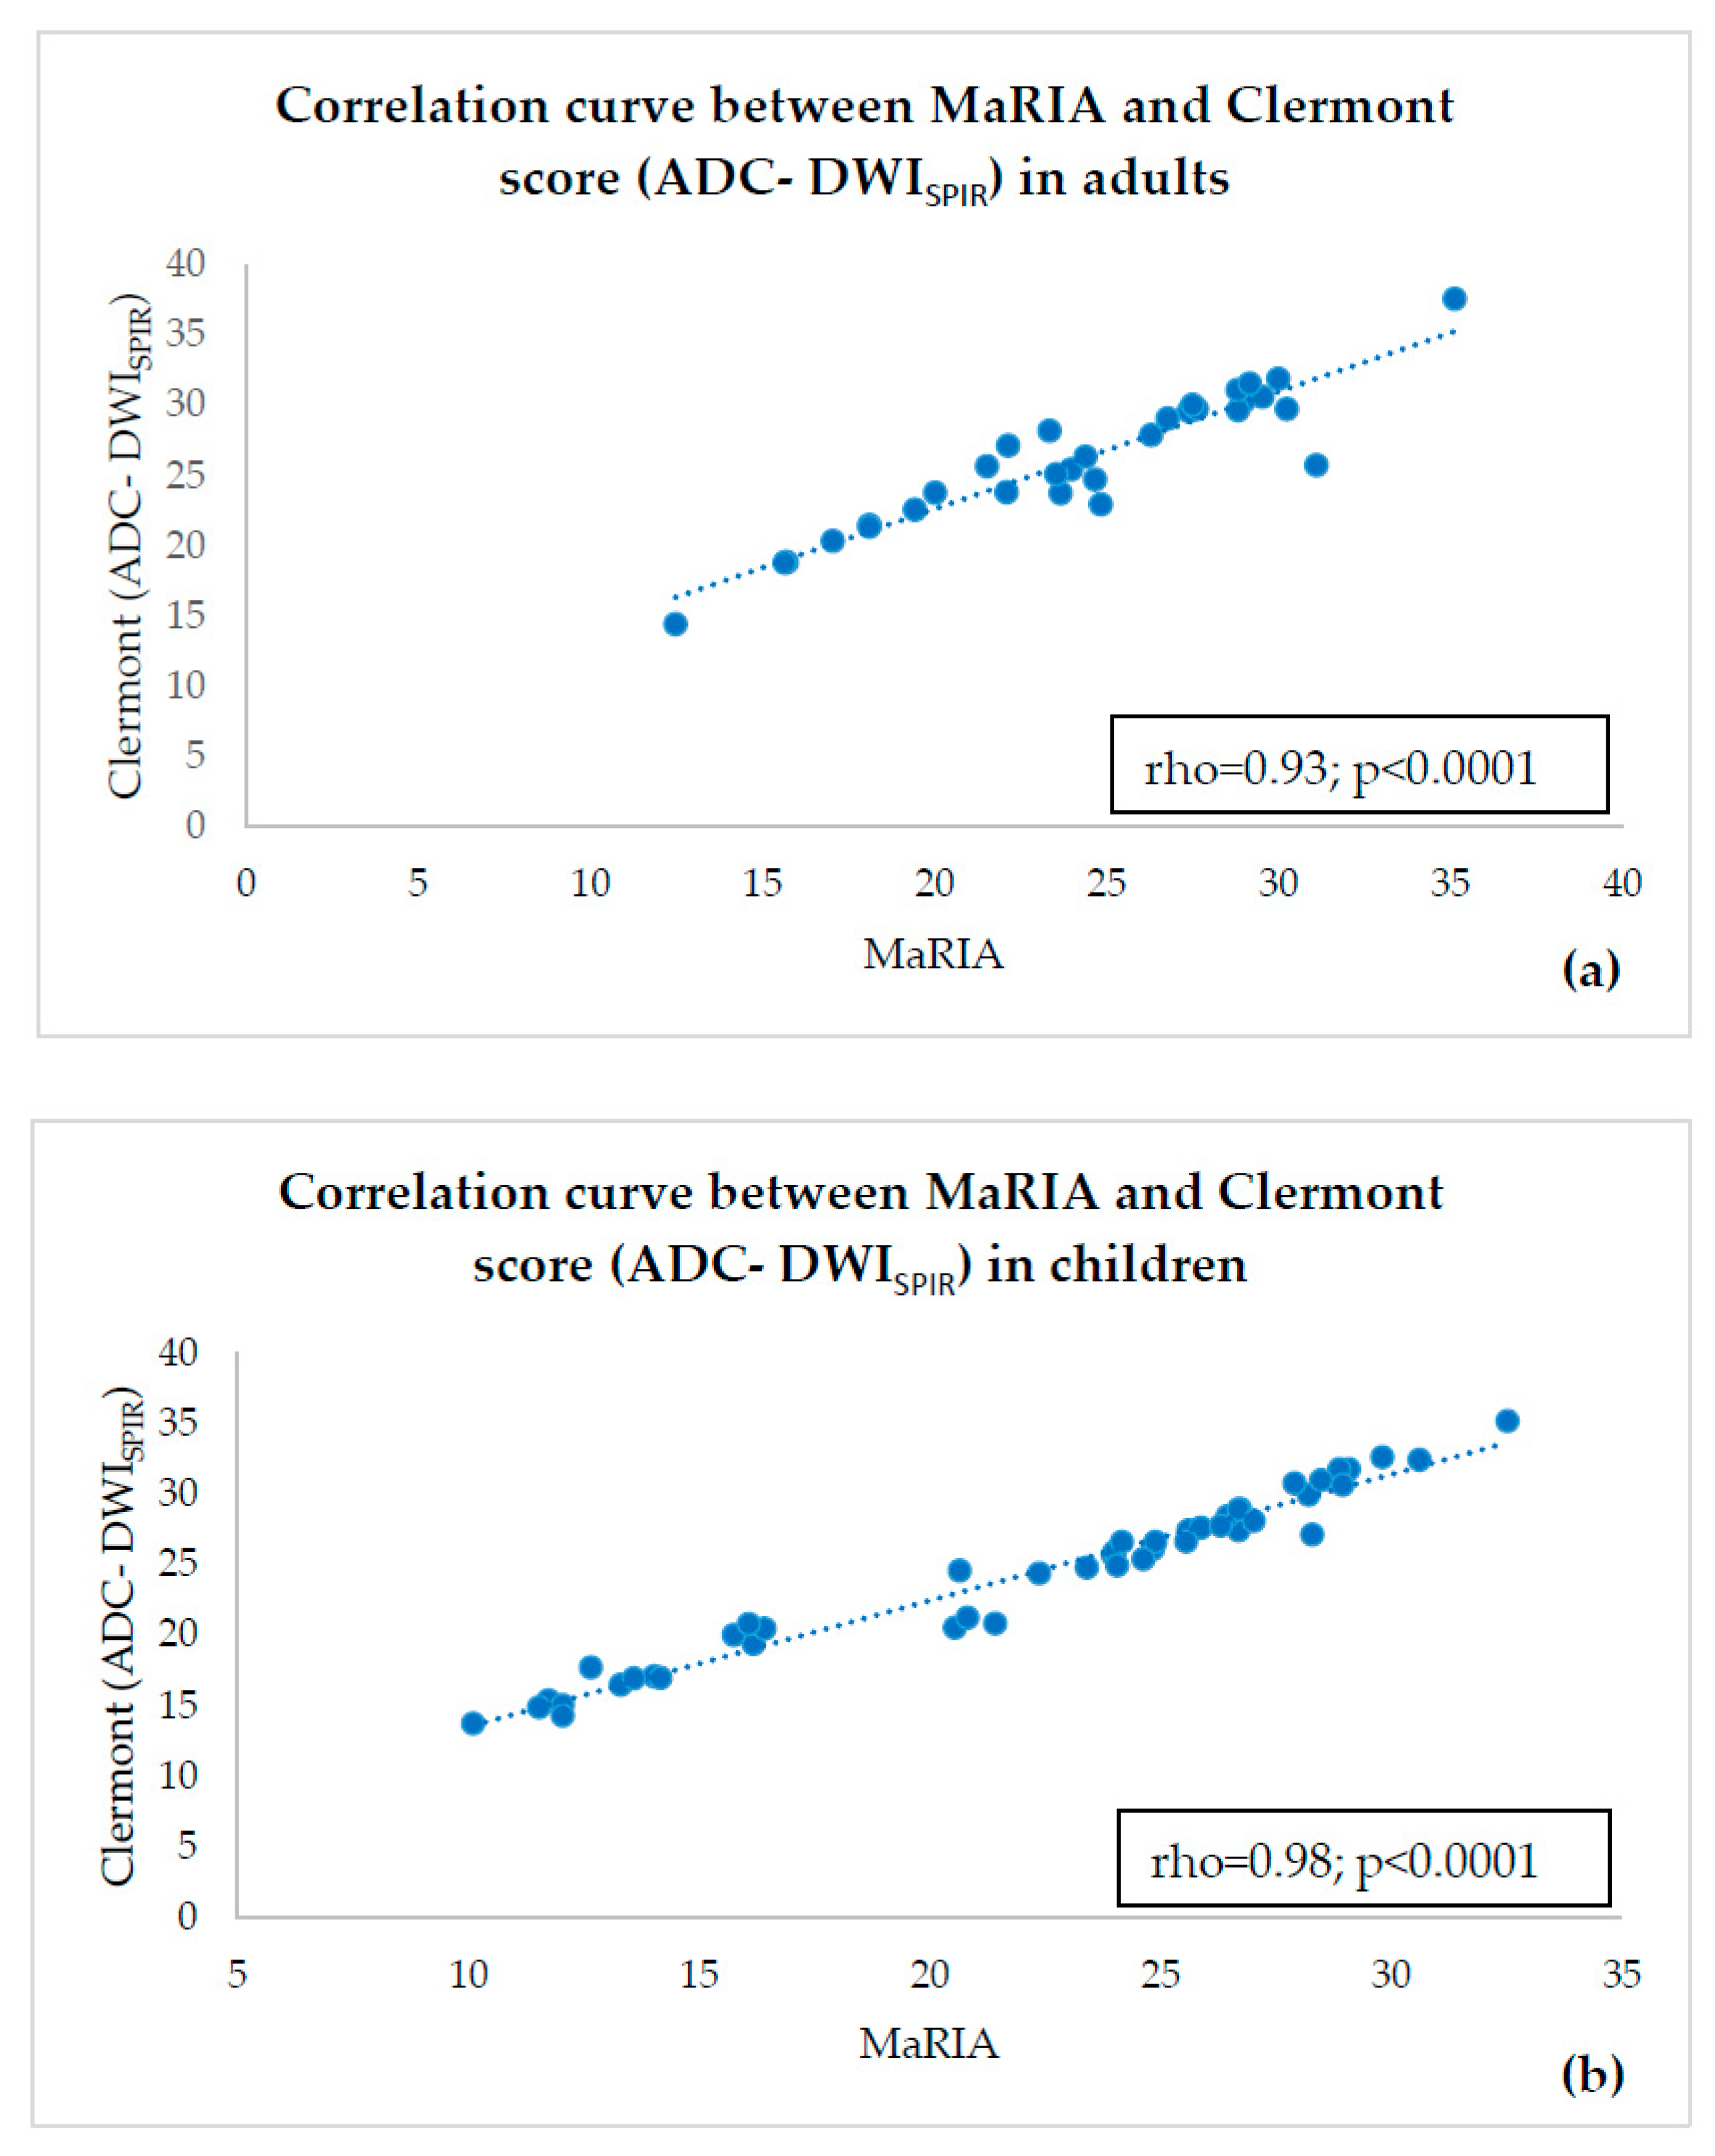

- estimating correlations of ADC-DWISPIR and ADC-DWISTIR values with the corresponding MaRIA, calculated from the contrast–enhanced sequences within the same bowel segments,

- calculating Clermont scores values based on ADC-DWISPIR and ADC-DWISTIR and estimating their correlation with MaRIA within the same bowel segments.